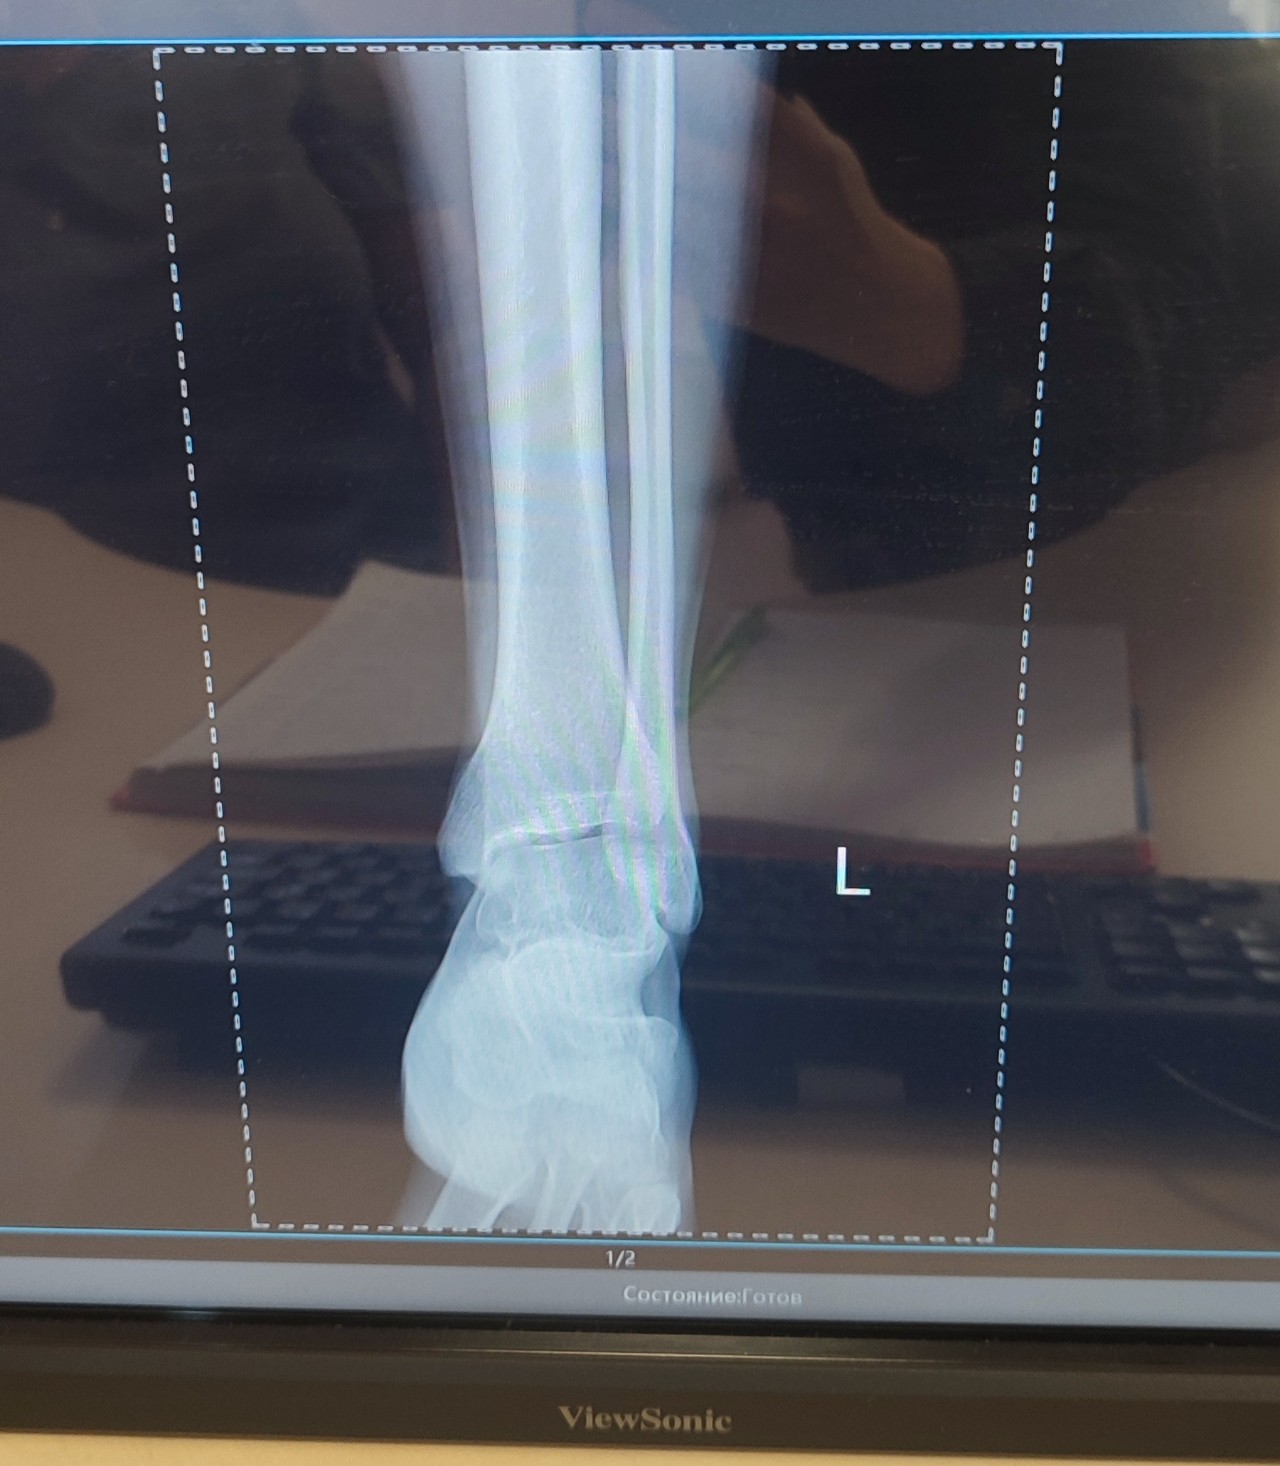

Жалобы: периодически болит и опухает левый ГСС, правый хрустит, болит боли в спине и покалывания в груди после нагрузки. Бывает предобморочное сознание. Часто болит живот и диарея. Кровь при дефекации. По телу несколько раз в год бывают красные пятна, раньше связывал их с солнцем. Частые эпизоды спонтанного стоматита. Зрение ухудшилось стало -2, 5 (за года на 1, 5 единицы - ортопед сказал, что это может быть связано с соединительной тканью).

Заключение у ортопеда: S-образный сколиоз фиксированный вправо-2 степени; плоскостопие.